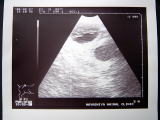

小さい黒い袋が3つ、つまり赤ちゃんは3匹確認!まだまだ、頭数ははっきりとしないけど、3匹以上ってこと?!(画面上には2つの袋が見えるよ) |

今日は病院へ。待合室では様々な思いが頭の中を巡っている。名前を呼ばれていざ診察室の中へ。妊娠の可能性、20日目を過ぎた頃からの食欲低下、嘔吐などの近況を話し終えたところで、先生がお腹を触診。そして、あまり多くは語らず、エコーマシーンを引っ張り出した。ボスとサブは映し出された画面に釘付け。画面の中には、見たことのある黒い袋が.

. . . . そして、先生が一言「妊娠してますね」。「やったー!おめでとうチョコ!!」。二人して顔がにんまり。チョコちゃん御懐妊。でも心配なことも言われてしまった。交配した日の割には赤ちゃんが小さいらしい。排卵が考えていたよりも遅かったのではないかということで、あまり気にしないようにとのこと。でも、そんな事言われてしまったら気にしてしまうぅ〜。